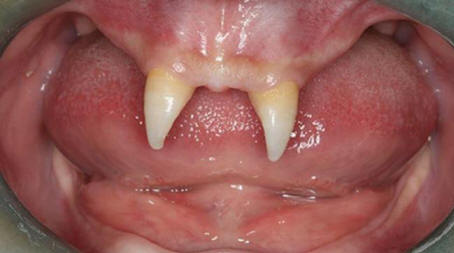

3. Teini-ikäinen on kasvanut omat vampyyrihampaat

Kiinalainen poika kasvatti kahta erittäin terävää etuhammasta saaden hänet näyttämään vampyrilta. Joulukuussa 2012 äiti nimeltä Wang Hui vei poikansa Wang Penfein paikalliselle sairaala tutkittavaksi. Chongqing Municipal Boy After syntymä on erittäin huonosti kasvavaa, ja hänen suussaan ilmestyi kaksi terävää keila.

Wang Hui yritti selvittää syyn näiden pojan ilmestymiseen epänormaalit muodostelmat ja vieraili lukemattomissa lääkäreitä, mutta se ei tuottanut suurta menestystä. Lääkärit alkaen Southwestern Hospital sairaalan mukaan hänen poikansa voidaan tehdä leikkaus vasta kun hänestä tulee aikuinen.

Tämän toimenpiteen kustannukset voivat vaihdella 70 000 – 80 000 RMB, se on noin 15 000 dollaria. Wang Huin mukaan hänen poikastaan on tulossa yhä enemmän vetäytyy ja taistelee usein luokkatovereiden kanssa, kuka kuiskaa häntä tai katsoa kysyntää hänelle.